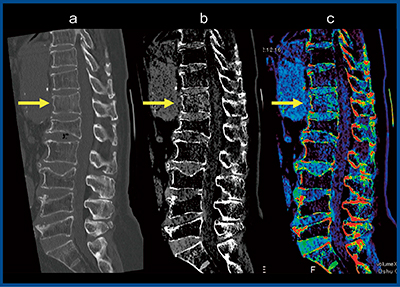

症例4は,腰椎椎体骨折。単純X線写真では骨折を描出できず,135kVpのMPR画像(図4 a→)では第1腰椎の椎体骨折がかろうじて認められるが,BBIでは一見して高吸収域を確認できる(図4 b→,c○)。このことから,先にBBIを見てからMPR画像を観察することで,読影時間の短縮化も可能になると思われる。また,症例5のような多椎体変形の腰椎椎体骨折では,骨折部位の確認が困難であるが,BBIを施行し高吸収域を見ることで,すぐに骨折箇所を同定できる(図5→)。

図4 症例4:腰椎椎体骨折

a:MPR画像 b:BBI(グレイスケール画像) c:BBI(カラー画像)